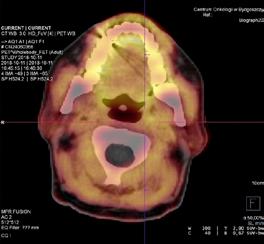

Badanie PET/CT łączy w sobie diagnostykę morfologiczną i metaboliczną poprzez jednoczesne wykonanie niskodawkowej tomografii całego ciała, obrazującej zmiany lityczne i ocenę zmian metabolizmu radioznacznika (najczęściej glukozy - 118F-fluorodeoksyglukoza, 18F-FDG) świadczących o aktywności choroby. Technika ta jest najskuteczniejszym narzędziem w identyfikowaniu zmian pozaszpikowych. Ponadto ma znaczenie rokownicze i jest przydatna

w monitorowaniu metabolicznej odpowiedzi na leczenie. Liczba i metabolizm zmian ogniskowych wykrytych w PET/CT wykonanym na wstępie leczenia indukcyjnego stanowi czynnik predykcyjny wyniku terapii (czasu wolnego od progresji i czasu przeżycia całkowitego) u pacjentów kwalifikujących się do transplantacji szpiku, a utrzymanie lub osiągnięcie statusu remisji w PET/TK po przeszczepie ma przełożenie na dłuższe czasy przeżycia.

Ryc. 4.3. 18F-FET PET/CT – solitary plasmacytoma migdałka podniebiennego lewego, miejscowo zwiększony wychwyt radioznacznika.

Ryc. 4.4. 18F-FET PET/CT – stan po zakończeniu leczenia.

W niektórych sytuacjach klinicznych interpretacja PET/ CT nie jest oczywista, potencjalnie obarczona błędem. Użycie 18F-FDG może być problematyczne w przypadku obrazowania zmian pozaszpikowych zlokalizowanych w regionach często objętych stanem zapalnym, między innymi w obrębie szyi (migdałki podniebienne), gdzie istnieje ryzyko uzyskania wyników fałszywie dodatnich. Wówczas korzystną alternatywę stanowią niestandardowe radioznaczniki (np. 18F-fluoro-etyl-L-tyrozyna, 18F-FET), które – w przeciwieństwie do FDG – nie ulegają kumulacji w miejscach zmienionych zapalnie, a przez to są bardziej specyficzne dla komórek nowotworowych. Należy pamiętać, że istnieje również ryzyko uzyskania wyników fałszywie ujemnych w przypadku przejściowej głębokiej supresji metabolizmu guza i konkurencyjnego hamowania wychwytu FDG z plazmocytów w sytuacji wzrostu glikemii, np. w trakcie steroidoterapii. Zmiany charakteryzujące się bardzo niskim stopniem wychwytu FDG, maskowane rozlanym wychwytem FDG lub w lokalizacji o silnej fizjologicznej aktywności FDG (np. w czaszce), mogą nie generować sygnału w badaniu PET.